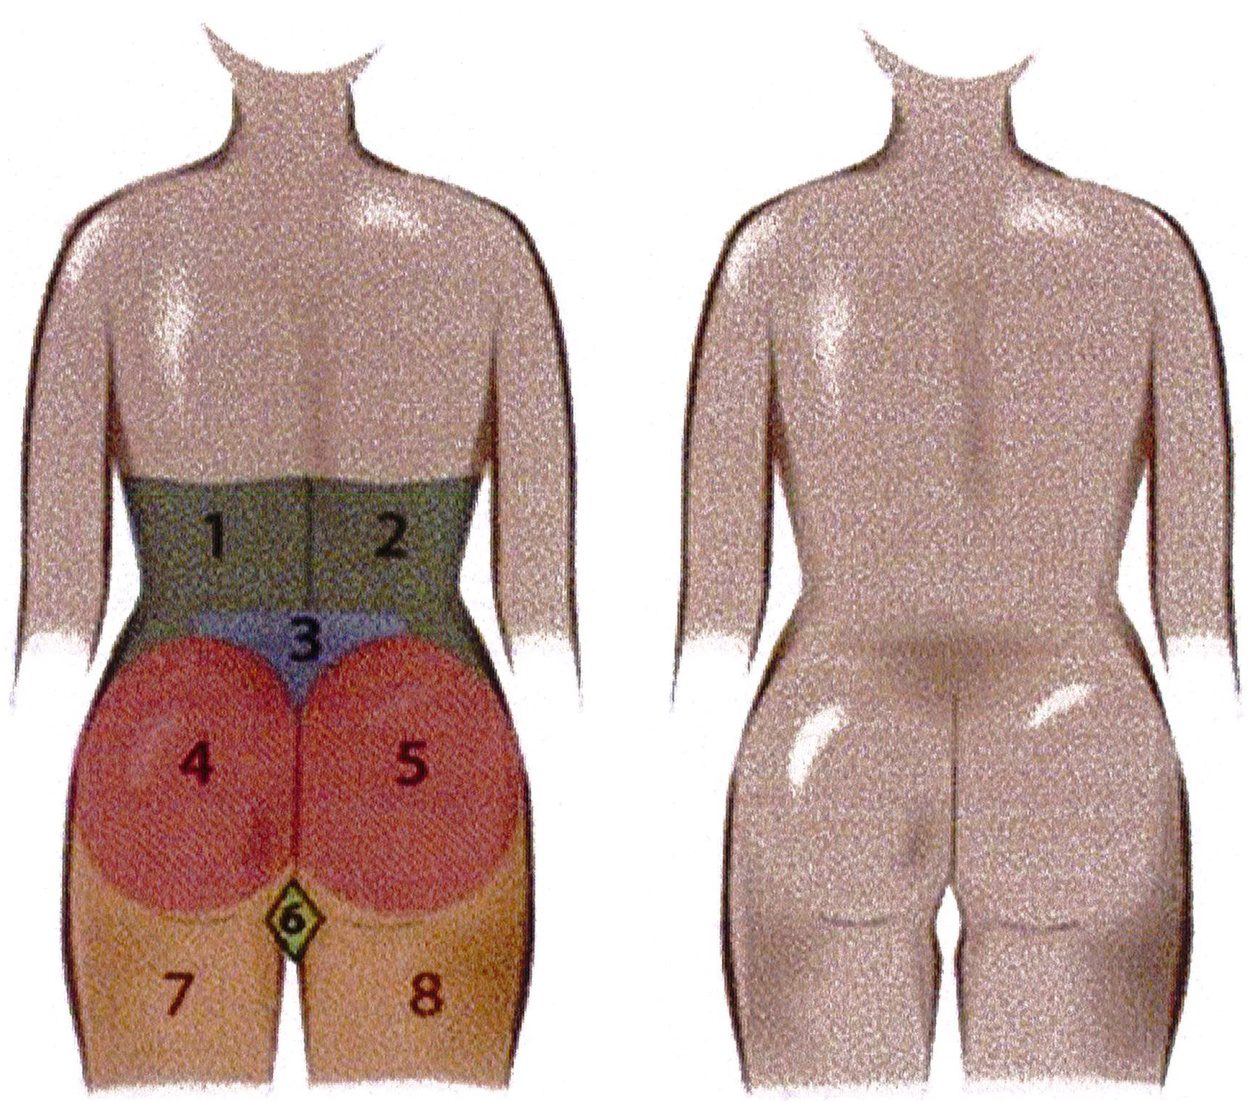

giao thoa 2 nếp lằn mông, 2 đơn vị mông đối xứng và 2 đơn vị đùi đối xứng (Hình 3). Khuyến khích việc phân tích giải phẫu cẩn thận và kỹ thuật phẫu thuật chính xác, cũng như giao tiếp tận tình với bệnh nhân để xác định nhu cầu của họ.

Các đơn vị thẩm mỹ vùng mông là khái niệm quy định các vùng thẩm mỹ khác nhau của mông. Hiểu được các đơn vị thẩm mỹ này và mối quan hệ của chúng với khu- ng chậu là điều tối quan trọng trước khi thực hiện nâng mông. Các đơn vị này được sử dụng để định hướng và xác định khu vực nào sẽ được nhận Mỡ, khu vực nào sẽ được hút mỡ, điều này sẽ ảnh hưởng tới kết quả, vì thế chúng ta cần thảo luận kỹ. Công trình đã xuất bản trước đây đã mô tả 10 đơn vị thẩm mỹ cho vùng sau (Hình 2), và một công trình khác đã mô tả 8 đơn vị thẩm mỹ vùng mông: 2 đơn vị mạn sườn, 1 đơn vị tam giác cùng, 1 đơn vị

Hình. 3. 8 đơn vị thấm mỹ vùng mông bao gôm 2 mạn sườn đối xứng 2 bên (1,2), 1 tam giác cùng (3), mông hai bên (4,5), 2 đùi sau đối xứng nhau (7 và 8), và 1 bộ phận giao thoa của 2 nếp lắn mông (hình thoi – 6) (Nguồn: Centeno RF. Gluteal aesthetic unit classification: a tool to improve outcomes in body contouring. Aes- thetic Surg J 2006;26(2):200-8)